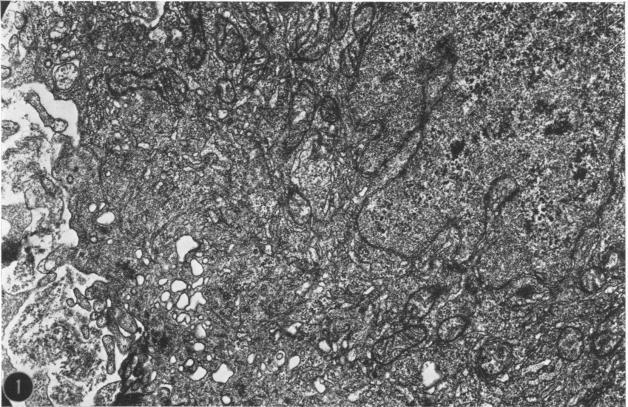

Ultrastructural observations on a new viral isolate, designated iguana virus, indicate that it is consistently present in intranuclear inclusions, possesses a +/- 115-nm nucleocapsid, ranges from 165 to 300 nm in diameter in the enveloped form, and exhibits cubic symmetry (probably 162 capsomeres). It is concluded that it is a herpes-type virus, the morphological evidence being in agreement with and supporting the biological and physical characteristics presented by Clark and Karzon. Several fine-structural features, among them the encapsidization of small 35-nm hexagonal bodies and the viral membrane envelope enclosure of cell-derived moieties are presented and discussed.

对一种新的病毒分离株(命名为鬣蜥病毒)的超微结构观察表明,它始终存在于核内包涵体中,具有约115纳米的核衣壳,包膜形式的直径范围为165至300纳米,并呈现立方对称(可能有162个壳粒)。得出的结论是,它是一种疱疹型病毒,形态学证据与克拉克和卡尔宗提出的生物学和物理特征一致并提供了支持。文中展示并讨论了几个精细结构特征,其中包括35纳米的小六角体的衣壳化以及细胞衍生部分的病毒膜包膜包裹。